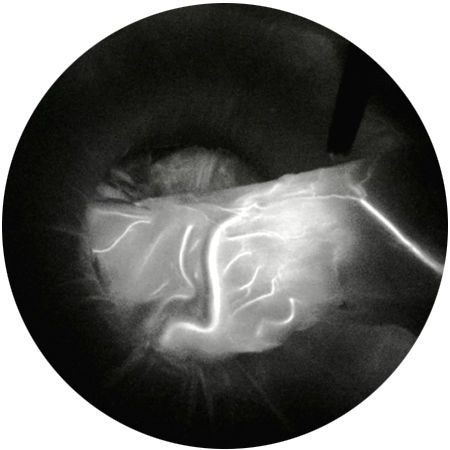

Monokromatik

Farklılıkları en iyi şekilde tespit edebilmek adına siyah bir zemin üzerinde NIR/ICG sinyalini gösterir.